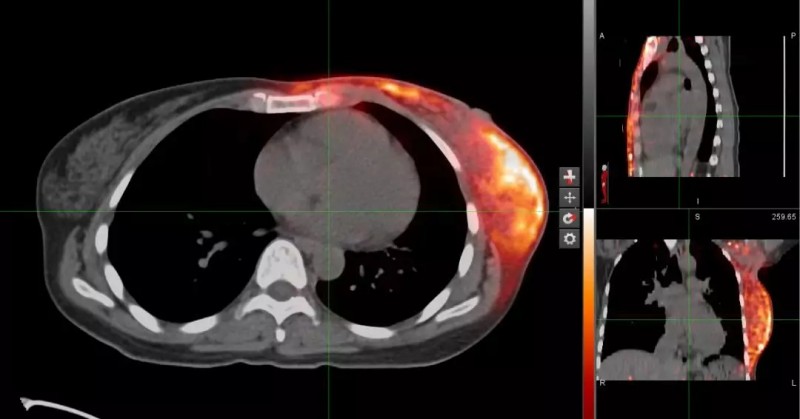

<< 质子放疗后 PETCT剂量验证图>>

明亮部分表示接受照射的人体组织

(照射剂量越大,亮度越高)